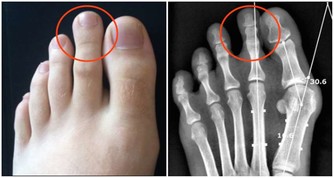

4、腳趾甲變厚

腳趾甲變厚,最有可能是灰指甲在作怪。

灰指甲又稱甲癬,是由真菌傳染到趾甲而引起的,且多發生在糖尿病患者、有循環問題和免疫問題的人身上。